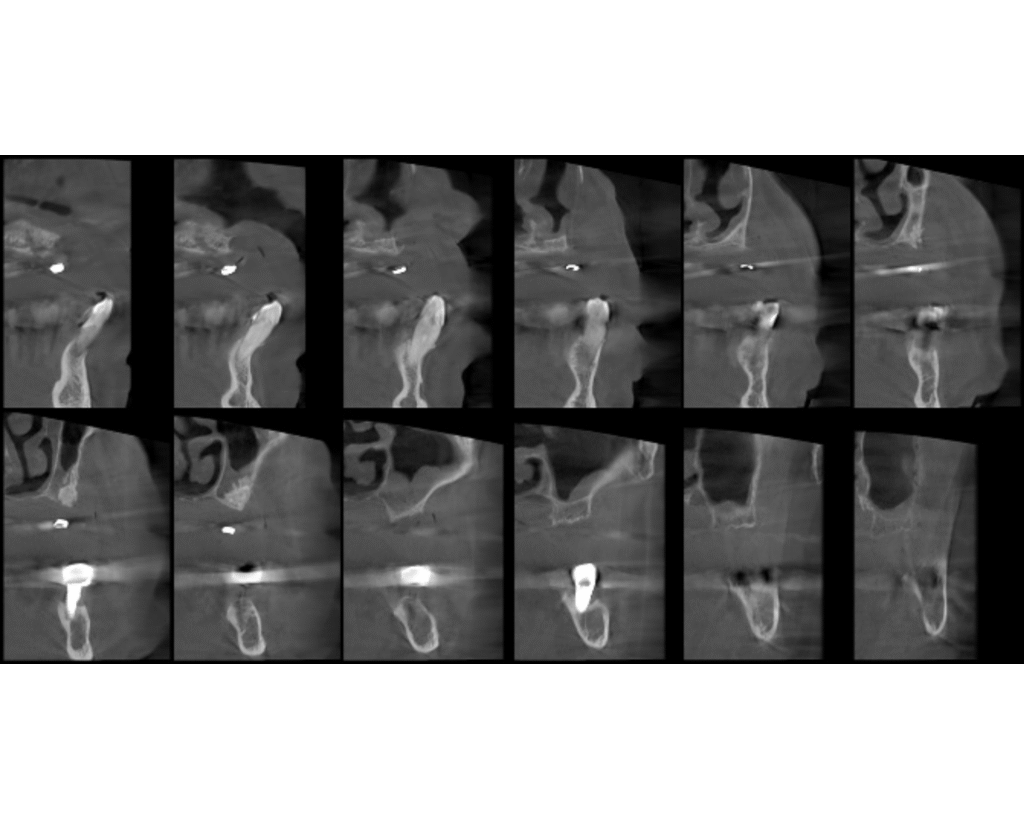

Radiográficamente se observa una atrofia severa de todo el maxilar superior, con pérdida del hueso total a nivel del seno maxilar derecho, probablemente por el fracaso de las intervenciones en el pasado, y áreas de apenas 1 mm de hueso en la zona antero superior. En el segundo cuadrante se observan restos de material, probablemente xenoinjerto, de los intentos de elevación sinusal en este lado. En la arcada inferior, se observa pérdida ósea generalizada, y acentuada a nivel del implante correspondiente al diente 46.